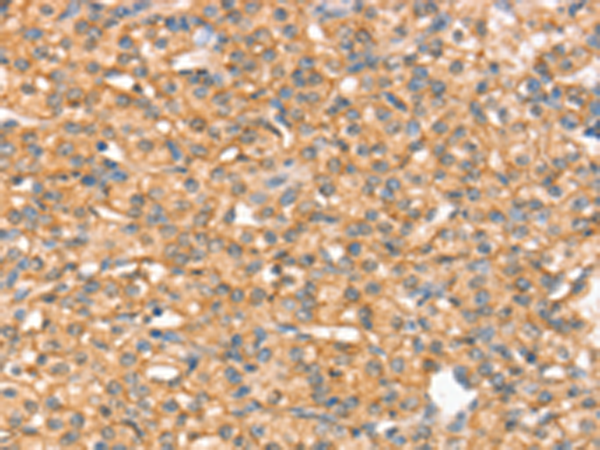

IHC positive control: |

Human prostate cancer |

IHC Recommend dilution: |

25-100 |